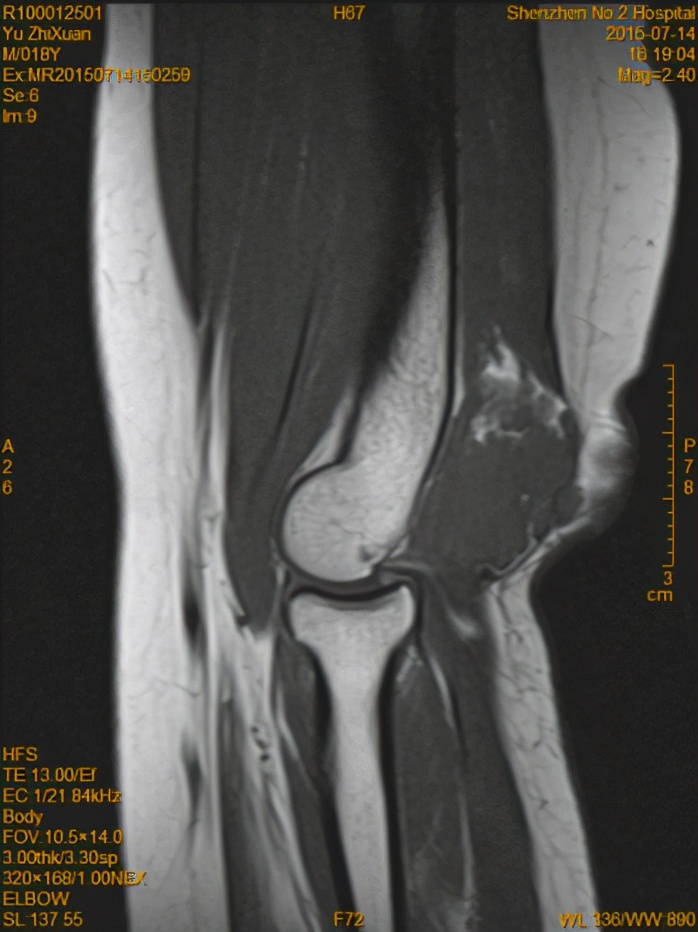

MR检查

(术前MR T2WI )

(术前MR T1WI )